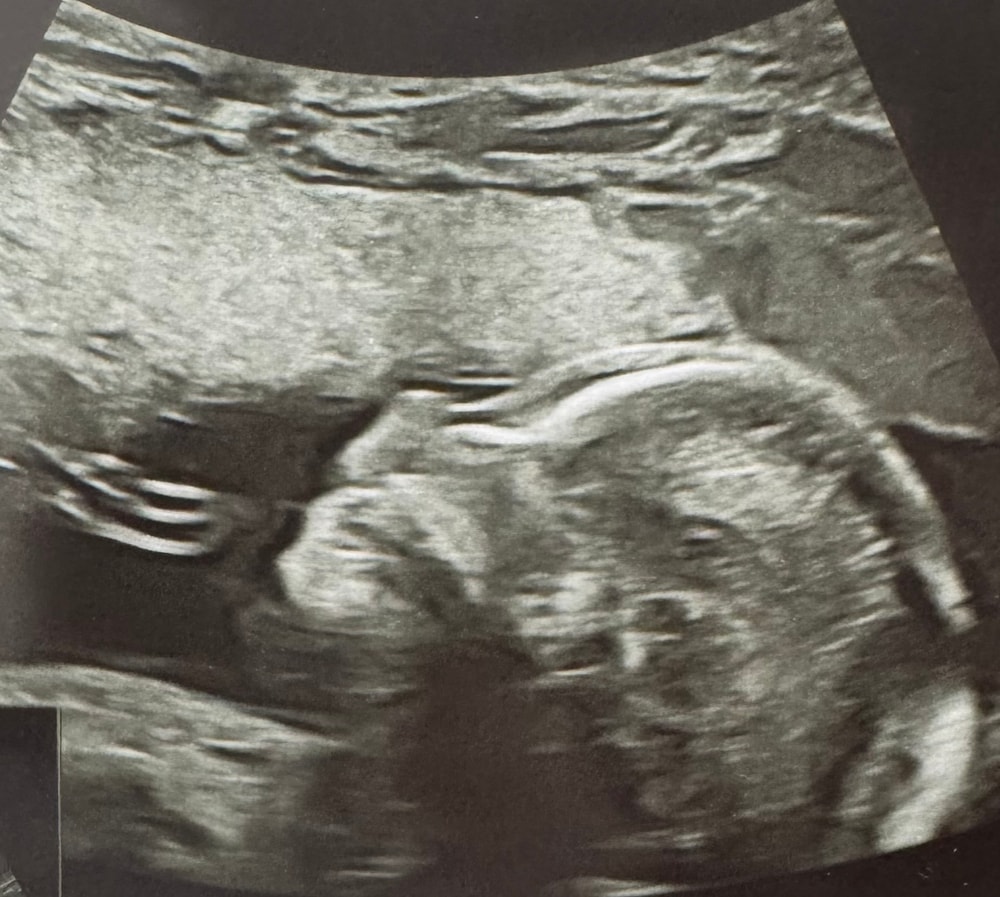

В итоге наш малыш мирно спал 🥰 в 12-то часов дня, весь в мать)) видели, как он сладко зевнул) и совсем не хотел поворачиваться, чтобы мы могли рассмотреть его со всех сторон.

УЗИ длилось минут 40 по итогу, на 20й минуте примерно мы все же разбудили это чудо, и он дал нам доступ к органам. К счастью, все отлично! Малыш компактный, 290г (врач предположила, что будет крошкой при рождении, килограмма 3). Органы все на месте, работают как часики. Сердечко стучит активно, четырехкамерное, со всеми сосудами и артериями. Не смогли рассмотреть клапаны аорты, но оставили это на третий скрининг) ножки длинные, ручки в кулаках, курносик.. нечто 🥹 это прекрасно, девочки)

Долго не хотел раздвигать ножки, чтобы подтвердить пол. Но все же сдался!) ждём мальчика 100%, пруфы в комментариях (осторожно, легкая эротика 😂).